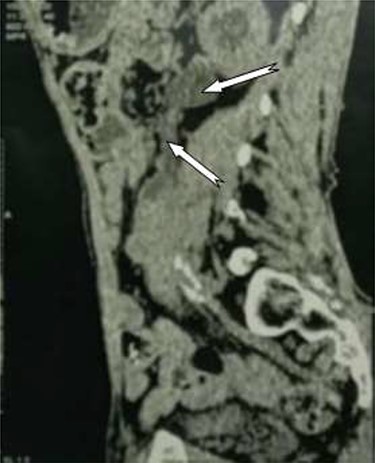

Abdomino-pelvic computed tomography scan revealed an enlarged left kidney, a lump in the lumbar ureter, and irregular thickening of the bladder wall. (Figs 1 and 2).

Tumor process at the expense of the kidney and the left urethra.